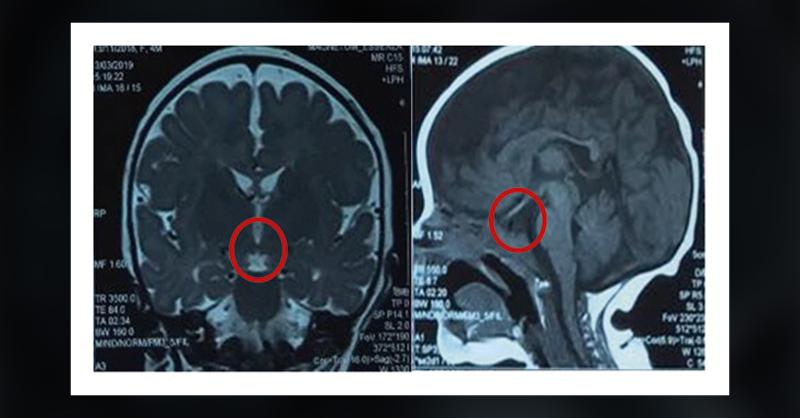

A 40-day-old girl was admitted for progressively worsening cholestatic jaundice, which began on her third day of life. She was born full term from a non-consanguineous marriage. Her perinatal history was unremarkable. Physical examination revealed jaundiced skin and sclera, dark urine, and pale stools, but no hepatomegaly or splenomegaly. There wer